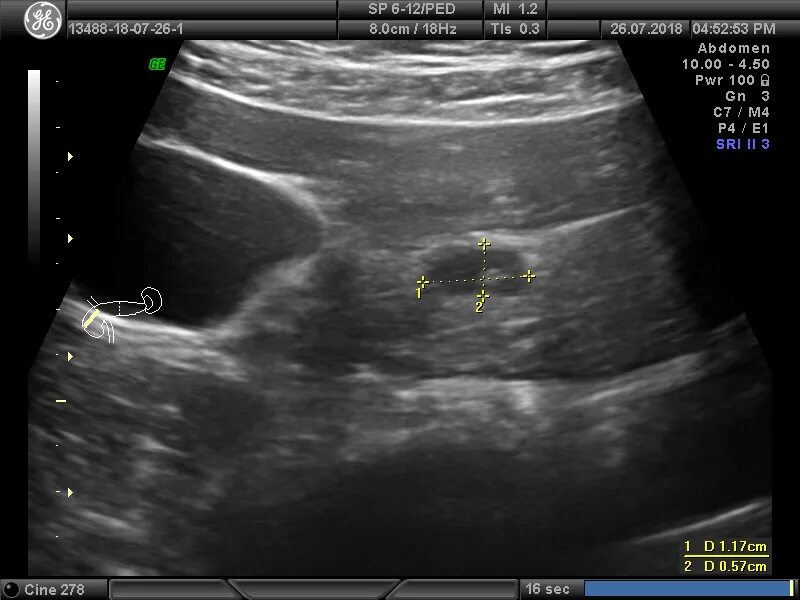

Диффузные изменения киста поджелудочной железы